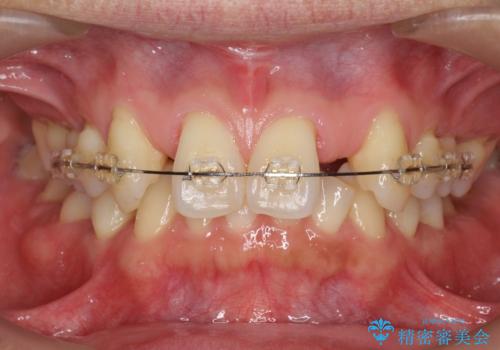

- 前歯部のすきっぱと歯並びが気になるので診て欲しいといらっしゃった方の症例です。

全顎矯正は御希望されなかったため、上顎前歯部のみの部分矯正とオールセラミッククラウンによる補綴を行いました。

今回用いたオールセラミッククラウンはジルコニアフレームという白い素材の上にセラミックを盛っているため、審美性が非常に高いのが特徴です。

また、ジルコニアは人工ダイヤモンドの材料にも使われているほど高い強度を持っており、そのためオールセラミッククラウンは審美性だけでなく、奥歯やブリッジの補綴も可能とするクラウンです。